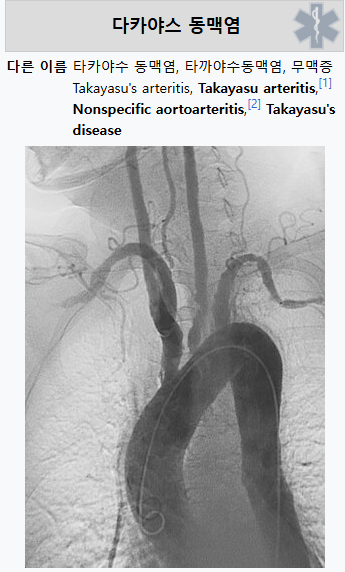

타카야수 동맥염(Takayasu Arteritis, TA)은 주로 큰 혈관, 특히 대동맥과 그 가지들에 염증이 생기는 희귀한 만성 염증성 질환입니다. 이 질환은 주로 20대에서 40대의 여성에게 많이 발생하며, 혈관의 염증이 지속되면 혈관이 좁아지거나 막혀 혈류 장애를 일으킬 수 있습니다.

**타카야수 동맥염(Takayasu Arteritis, TA)**은 대동맥과 그 주요 가지들(상완동맥, 경동맥 등)에 염증이 생기는 희귀한 만성 혈관염입니다. 이 질환은 자가 면역 질환으로 분류되며, 면역 시스템이 자신의 혈관을 잘못 인식하고 공격하여 염증 반응을 일으킵니다. 염증이 진행됨에 따라 동맥벽이 두꺼워지거나 좁아지거나 막히게 되며, 그로 인해 혈류가 제한되고, 장기(특히 심장, 뇌, 신장)로 가는 혈액 공급이 부족해질 수 있습니다. 그 결과 심혈관계 질환(협심증, 심장마비 등), 뇌졸중, 고혈압과 같은 심각한 합병증을 초래할 수 있습니다.